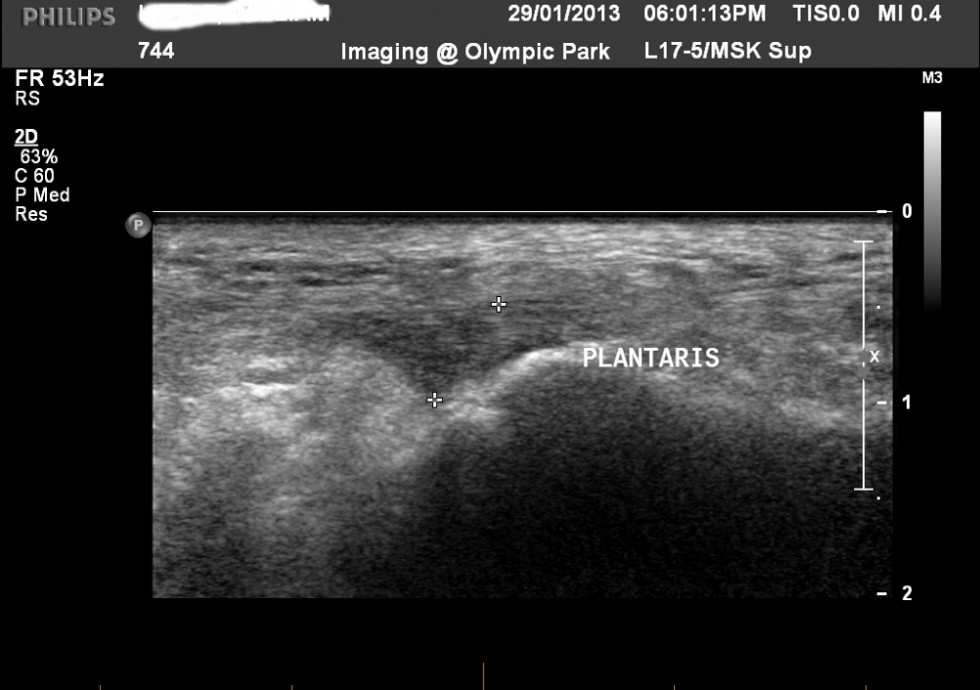

TENDÓN DEL MUSCULO PLANTAR

Puede manifestarse como dolor en el tendón plantar, o irritación / compresión del tendón medio de Aquiles desde tendón del plantar. El dolor en el tendón plantar no es común – vea un ejemplo de patología plantar insercional en uno de mis pacientes (Figura 6) – él señaló que el dolor se ubicaba en un lugar muy específico en la inserción medial de Aquiles, inyectamos solución salina de alto volumen y nunca regresó, a pesar de estar 2 años en competición de 400 metros. Los problemas más comunes del musculo plantar implican la compresión del tendón de Aquiles. Pueden ser síntomas típicos del tendón de Aquiles, pero es más probable que se trate de un dolor medialmente localizado y una patología de Aquiles medialmente localizada. Los síntomas pueden aparecer al final del rango de dorsiflexión debido a la compresión del tendón. Puede asociarse con una mayor pronación del pie en su función.

single-image

6 – tendón plantar hipoecoico y aumentado de volumen vista medial al talón de Aquiles en el calcáneo superior